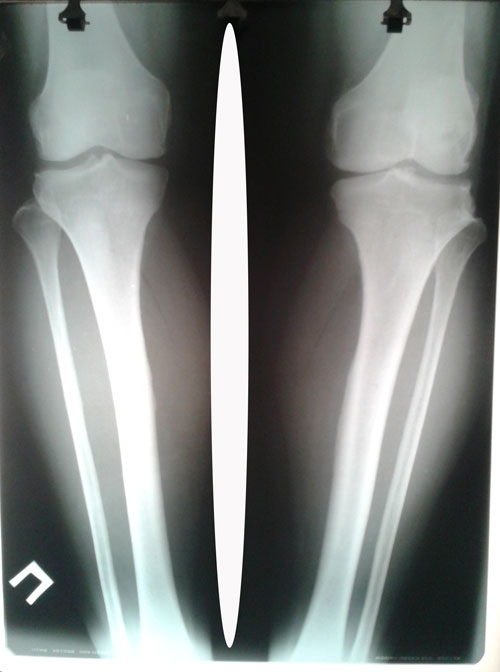

Рентген до операции.

20160709_125518.jpg